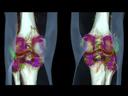

The question is: What makes True Dual Energy stand out? Look for these three criteria: crisp images with the option for even sharper contrast and significant artifact reduction; no extra dose in either Single Source or Dual Source Dual Energy scans, and a broad applicability for virtually all clinical questions and patients.

So if you want to highlight, characterize, quantify, and differentiate material, don’t settle for less. True Dual Energy offers you leading technology from the company that pioneered it – and that’s DEfinitely Siemens.

Discover Dual Energy (DE) spectral imaging. It’s the difference between images and answers. Visualization and characterization. Qualification and quantification. Built into all of our CT scanners, it delivers powerful performance, incredible versatility for your entire patient population, and exceptional ease-of-use – all while integrating seamlessly with your current workflow.